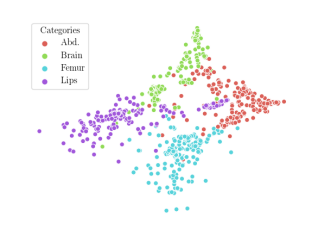

We compare the -distance of categorical features and domain features. Fig. 5 (a) shows that domain difference is higher in domain features than in categorical features. This indicates that domain features contain more domain information whereas categorical features are more domain-invariant. Fig. 6 shows the t-SNE plot of categorical features in both domains for MIDNet. From Fig. 6 (a), we observe that the categorical features learned by MIDNet enable the anatomical classification. Fig. 6 (b) shows that the learned categorical features are domain-invariant.

In addition, we utilize t-SNE plots for feature visualization in Fig. 10. Comparing Fig. 10 (a) and Fig. 10 (b), we observe that with mutual information disentanglement, (1) samples from the same category are more tightly clustered (see the top row) and (2) the source domain and the target domain are overlap more (see the bottom row). This indicates that mutual information disentanglement is important for learning categorical-focused and domain-invariant features. Fig. 10 (a), (c)-(d) show that the proposed method outperforms other state-of-the-art methods for learning category-discriminative and domain-invariant features, especially for unseen categories in the target domain (e.g., (a) vs. (d)).